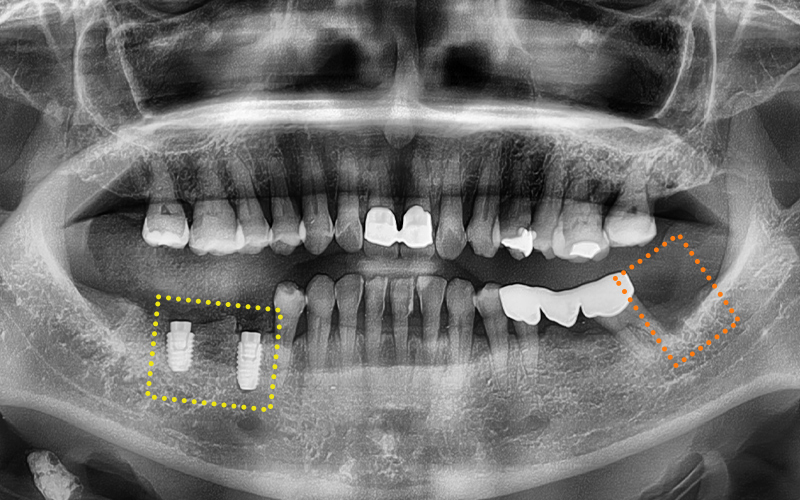

사랑니는 발치하고,

반대측엔

임플란트 식립도 진행한 모습인데요.

🦷 최종 계획

✔ 좌측 아래 사랑니

ㅡ> 감염 소견 있어 즉시 발치

✔ 우측 아래 기존 브릿지

ㅡ> 제거 후 발치 및 임플란트 식립 계획

임플란트가 잇몸뼈에 잘 고정될 수 있도록

충분한 시간을 기다려주었고,

크라운 (보철물) 작업을 위하여

맞춤형 지대주를 체결한 모습입니다.